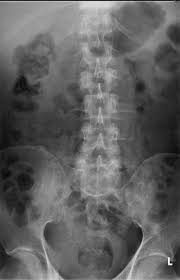

Metastatic Disease Of Spine Pathology Orthobullets

Metastatic Disease Of Spine Pathology Orthobullets from upload.orthobullets.com

Metastatic Spine Tumors

Metastatic Spine Tumors from embed.widencdn.net